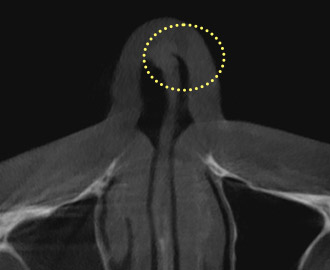

Nasal Valve

Stenosis

Nasal valve stenosis

occurs when the

upper

portion of the nasal cavity,

responsible for controlling

airflow,

becomes narrow,

causing nasal

congestion

and sleep disturbances.

Treatment Points

Expand the narrowed

nasal

valve space to its

normal range,

enabling

smooth breathing.